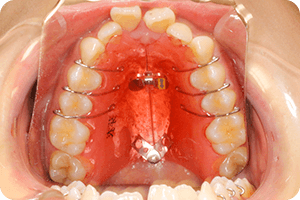

矯正治療を行うために、「上下の顎の形状」「上下の顎のズレ」「歯の角度」「噛み合わせの状態」などを正確に測り、治療の計画を立て、治療中の経過確認していく必要があります。これらを測定するためのレントゲン写真の規格が「セファログラム」であり、当院ではこの撮影装置を完備しています。